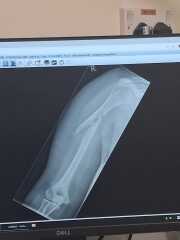

I had to google what a brace looks like, one of these?

it sounds same as the "sling" my dad had. He was sure that couldn't be correct treatment and enough, but he got same treatment in Italy & in USA so then he accepted it.

This is the brace. Its worn under clothes so the foam stuff is direct on skin. Hang on and ill find a photo of the reaction

Broken arm and dont trust Dr's after they've consistently messed up.

Br0kenarm · 03/04/2026 10:56

Hello again everyone. Just thought i'd update you all. In January they said that it was calcifying well and I was discharged even though I could barely move it, felt it clicking etc.

Two physio sessions in and they thought the tendon had been torn so sent me to a specialist clinic and discovered it was still broken and actually worse than when it had happened. I had to have a plate and screws put in abd my arm stapled. 1 week in my arm feels so much better already and I can also move it more than I could last week.

My point is, if things dont feel right then argue it.